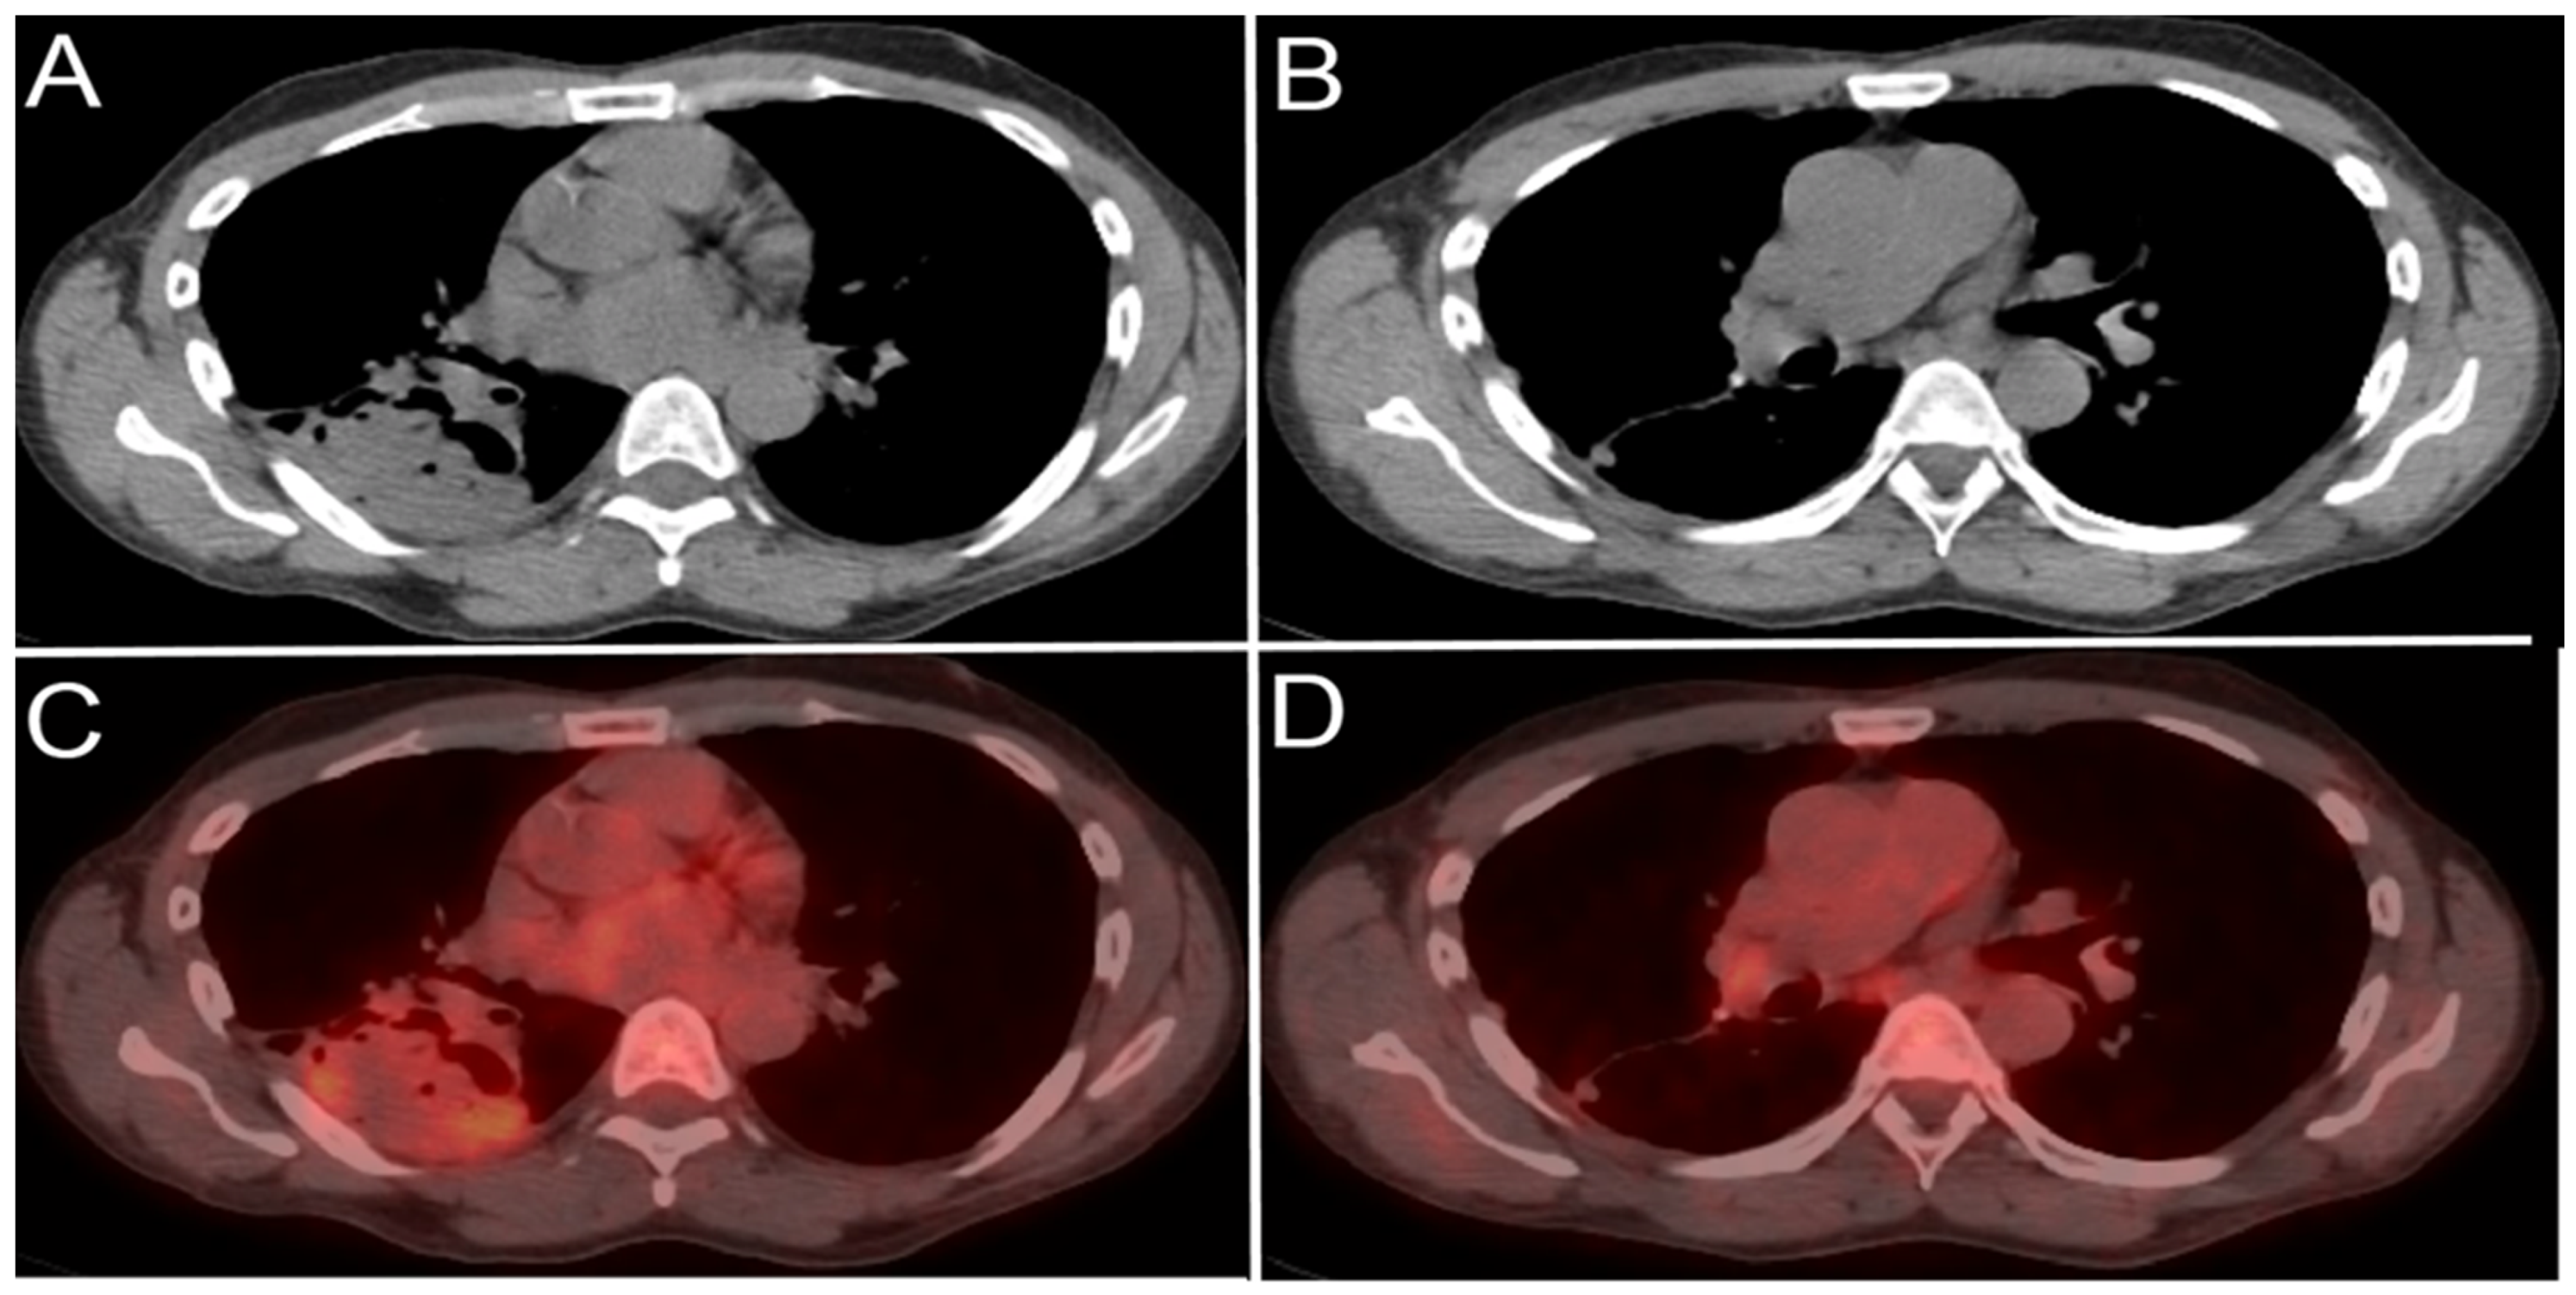

- Mittra, E.; Quon, A. Positron Emission Tomography/Computed Tomography: The Current Technology and Applications. Radiol. Clin. N. Am. 2009, 47, 147–160. [Google Scholar] [CrossRef]

- Vallabhajosula, S. 18F-Labeled Positron Emission Tomographic Radiopharmaceuticals in Oncology: An Overview of Radiochemistry and Mechanisms of Tumor Localization. Semin. Nucl. Med. 2007, 37, 400–419. [Google Scholar] [CrossRef] [PubMed]

- Liu, B.; Gao, S.; Li, S. A Comprehensive Comparison of CT, MRI, Positron Emission Tomography or Positron Emission Tomogra-phy/CT, and Diffusion Weighted Imaging-MRI for Detecting the Lymph Nodes Metastases in Patients with Cervical Cancer: A Me-ta-Analysis Based on 67 Studies. Gynecol. Obstet. Investig. 2017, 82, 209–222. [Google Scholar] [CrossRef] [PubMed]

- Choi, H.J.; Ju, W.; Myung, S.-K.; Kim, Y. Diagnostic performance of computer tomography, magnetic resonance imaging, and positron emission tomography or positron emission tomography/computer tomography for detection of metastatic lymph nodes in patients with cervical cancer: Meta-analysis. Cancer Sci. 2010, 101, 1471–1479. [Google Scholar] [CrossRef]

- Riegger, C.; Koeninger, A.; Hartung, V.; Otterbach, F.; Kimmig, R.; Forsting, M.; Bockisch, A.; Antoch, G.; Heusner, T.A. Comparison of the Diagnostic Value of FDG-PET/CT and Axillary Ultrasound for the Detection of Lymph Node Metastases in Breast Cancer Patients. Acta Radiol. 2012, 53, 1092–1098. [Google Scholar] [CrossRef] [PubMed]

- Cochet, A.; Dygai-Cochet, I.; Riedinger, J.-M.; Humbert, O.; Berriolo-Riedinger, A.; Toubeau, M.; Guiu, S.; Coutant, C.; Coudert, B.; Fumoleau, P.; et al. 18F-FDG PET/CT provides powerful prognostic stratification in the primary staging of large breast cancer when compared with conventional explorations. Eur. J. Nucl. Med. Mol. Imaging 2014, 41, 428–437. [Google Scholar] [CrossRef]